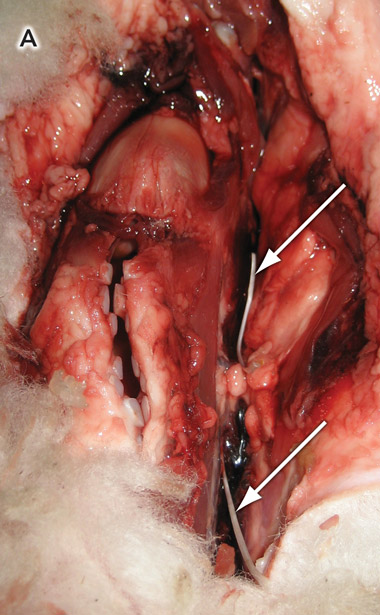

The specimen was prepared by removing excess wool and dissecting the laryngopharynx. The fishbones were placed in the paratracheal tissues and adjacent to the larynx (Box 2, A).

The positioning of the bones adjacent to the larynx or in the paratracheal tissue was thought to be a reasonable approximation to the clinical situation. The x-ray radiation would have to pass through the same series of tissue planes before producing an image. Placing the bones in the aerodigestive tract itself would create technical difficulties in the positioning and could lead to significant variabilty of final location of the bones. We did not attempt to identify the anatomical positions in which the bones would be most or least easily visualised. A standard location was preferred.